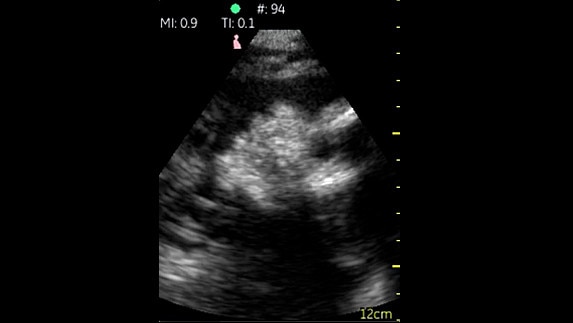

Fazlı Kardiyak